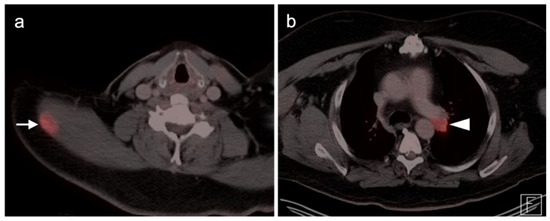

- Umemura, H.; Yamasaki, O.; Kaji, T.; Hamada, T.; Otsuka, M.; Asagoe, K.; Iwatsuki, K. Prognostic value of 18 F-fluorodeoxyglucose positron emission tomography/computed tomography in patients with cutaneous angiosarcoma: A retrospective study of 18 cases. J. Dermatol. 2017, 44, 1046–1049. [Google Scholar] [CrossRef] [Green Version]

- Tokmak, E.; Özkan, E.; Yağcı, S.; Kır, K.M. F18-FDG PET/CT Scanning in Angiosarcoma: Report of Two Cases. Mol. Imaging Radionucl. Ther. 2011, 20, 63–66. [Google Scholar] [CrossRef]